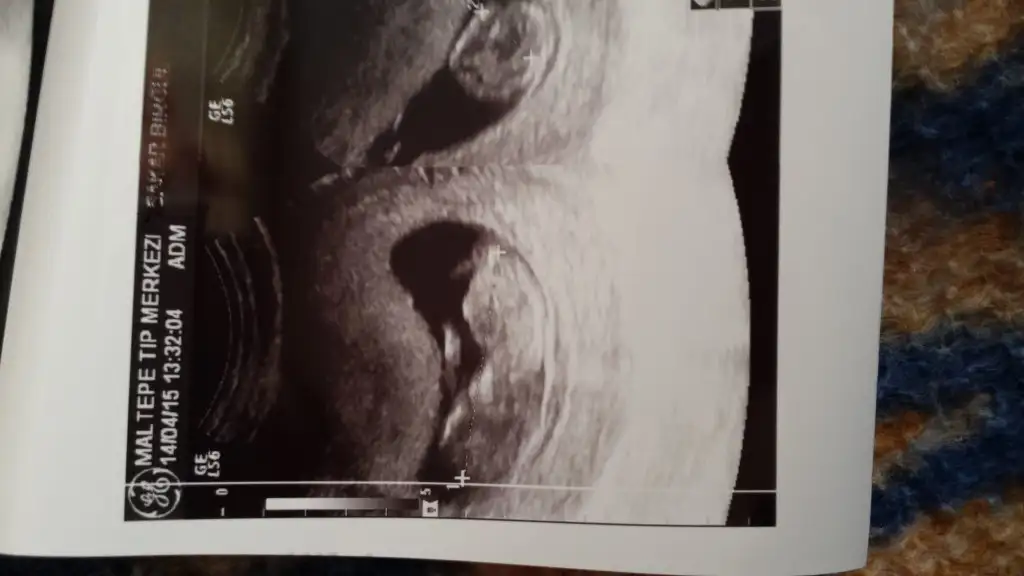

Banada Bakarmisiniz

Benim ki bu

• IMG-20150413-WA0007.webp

IMG-20150413-WA0007.webp

17,6 KB · Görüntüleme: 141

Ben devlete gittigim için ultrason görüntülerini vermediler hic..ilk defa özele gittim o verdi bu son görüntüyü 18 haftalık dedi